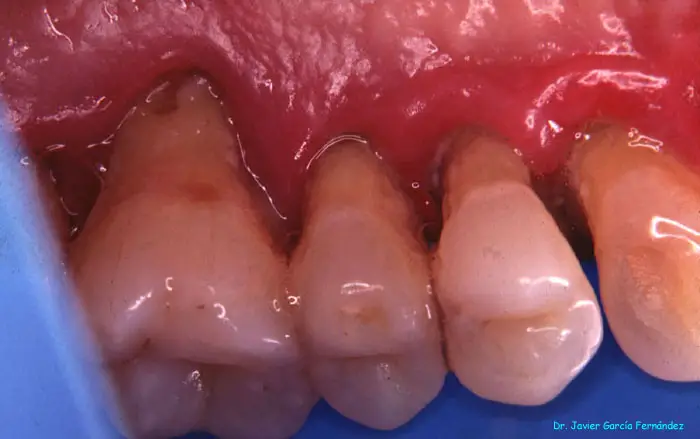

image020